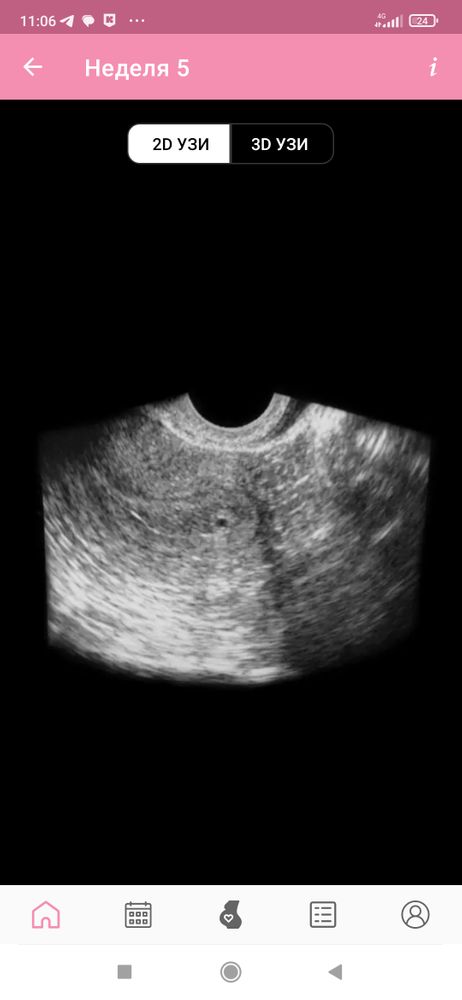

Примерно такое было УЗИ сегодня, но врач резко убрала датчик когда я увидела это